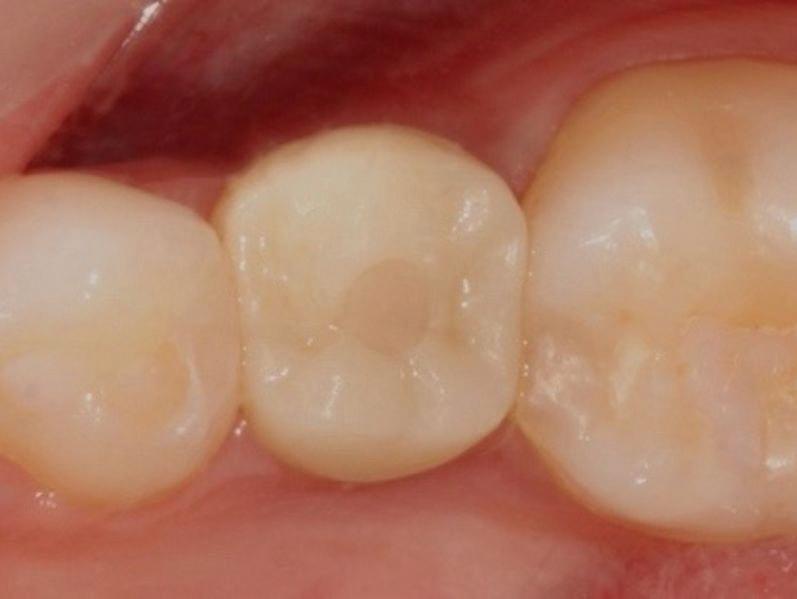

Estelite Asteria (Tokuyama)One of my favourite composite resin materials is Asteria which is a light-cured radiopaque composite for universal use. It considerably simplifies multilayer techniques yet delivers outstanding aesthetics with excellent polishability. Unlike mul tilayer techniques used with conventional composites, Asteria uses only 2 layers for optimal results without compromising aesthetics. The microstructure of the material produces a light diffusion that helps blend in with the natural tooth structure. The chameleon like nature of the material allows a blending of the materials to natural tooth structure and it allows excellent polishability which retains its lustre over time.